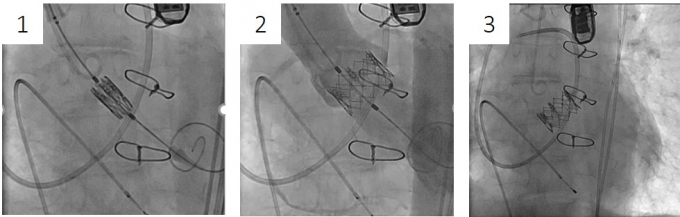

1. バルーン拡張型人工弁

(1)風船カテーテルの上にかしめた人工弁を弁輪部に配置し、(2)風船を拡張して留置したうえ、(3)風船を縮小させ、回収します。

(動画提供:エドワーズライフサイエンス合同会社)